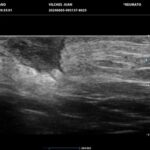

La HS es una enfermedad crónica, inflamatoria inmunomediada, sistémica, recurrente y debilitante de los folículos pilosos terminales con origen en las glándulas apocrinas de estos. Presenta habitualmente lesiones dolorosas, profundas e inflamadas, localizadas más frecuentemente en las regiones axilares, inguinales y anogenitales. El 80% de las lesiones tienen ubicación profunda de difícil acceso al examen físico. Su diagnóstico es clínico pero el ultrasonido (US) de alta resolución con Doppler es un método que cumple actualmente un rol esencial para establecer el diagnóstico, estadificar la enfermedad y detectar actividad, incluso en el caso de lesiones no pesquisadas en el examen físico. También nos permite monitorear el estado y la progresión de la HS, facilitando la evaluación rápida de distintos enfoques terapéuticos. Incluso, los cambios ecográficos pueden modificar la conducta terapéutica.

Los hallazgos ecográficos más relevantes son el ensanchamiento de folículos pilosos, engrosamiento y ecogenicidad anormal de la dermis, nódulos pseudoquísticos dérmicos, colecciones líquidas y tractos fistulosos. Por otro lado, el US nos permite valorar la localización exacta y extensión de las lesiones, su ecogenicidad, el grado de vascularización al examen Doppler y las eventuales complicaciones, e incluso la modificación de las lesiones en respuesta a la terapéutica instaurada. La HS se estadifica clínicamente mediante la clasificación de Hurley y los hallazgos ecográficos muestran correlación con cada estadio clínico.

El diagnóstico ecográfico resulta de importancia diagnóstica, tal es así que la ecografía de alta resolución y el estudio Doppler han ocupado un lugar preponderante en los últimos años. La ecografía de la piel permite identificar lesiones no encontradas en el examen físico, evaluando de manera fehaciente su extensión anatómica. El empleo de la ecografía en la HS es ideal, ya que el 80% de las lesiones ocurren en las capas más profundas y no en la superficie de la piel. Permite evaluar la localización exacta y extensión de las lesiones, su ecogenicidad, el grado de vascularización al examen Doppler, las eventuales complicaciones, e incluso la respuesta terapéutica.

El estudio ecográfico de alta resolución con Doppler tiene un rol fundamental en la categorización de las lesiones de HS en profundidad, incluso las subclínicas. Debemos incluir al US como técnica de elección para estadificar y monitorear pacientes con HS, ya que nos permite acceder a un diagnóstico rápido de lesiones típicas con las que podremos, en conjunto con la clínica, estadificar y seguir en el tiempo a los pacientes.